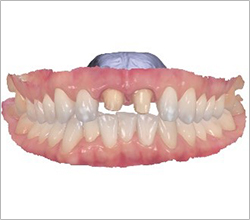

다양한 임플란트 치료 사례

#전체 임플란트

-

BEFORE: 2022.12.15

AFTER: 2023.02.23